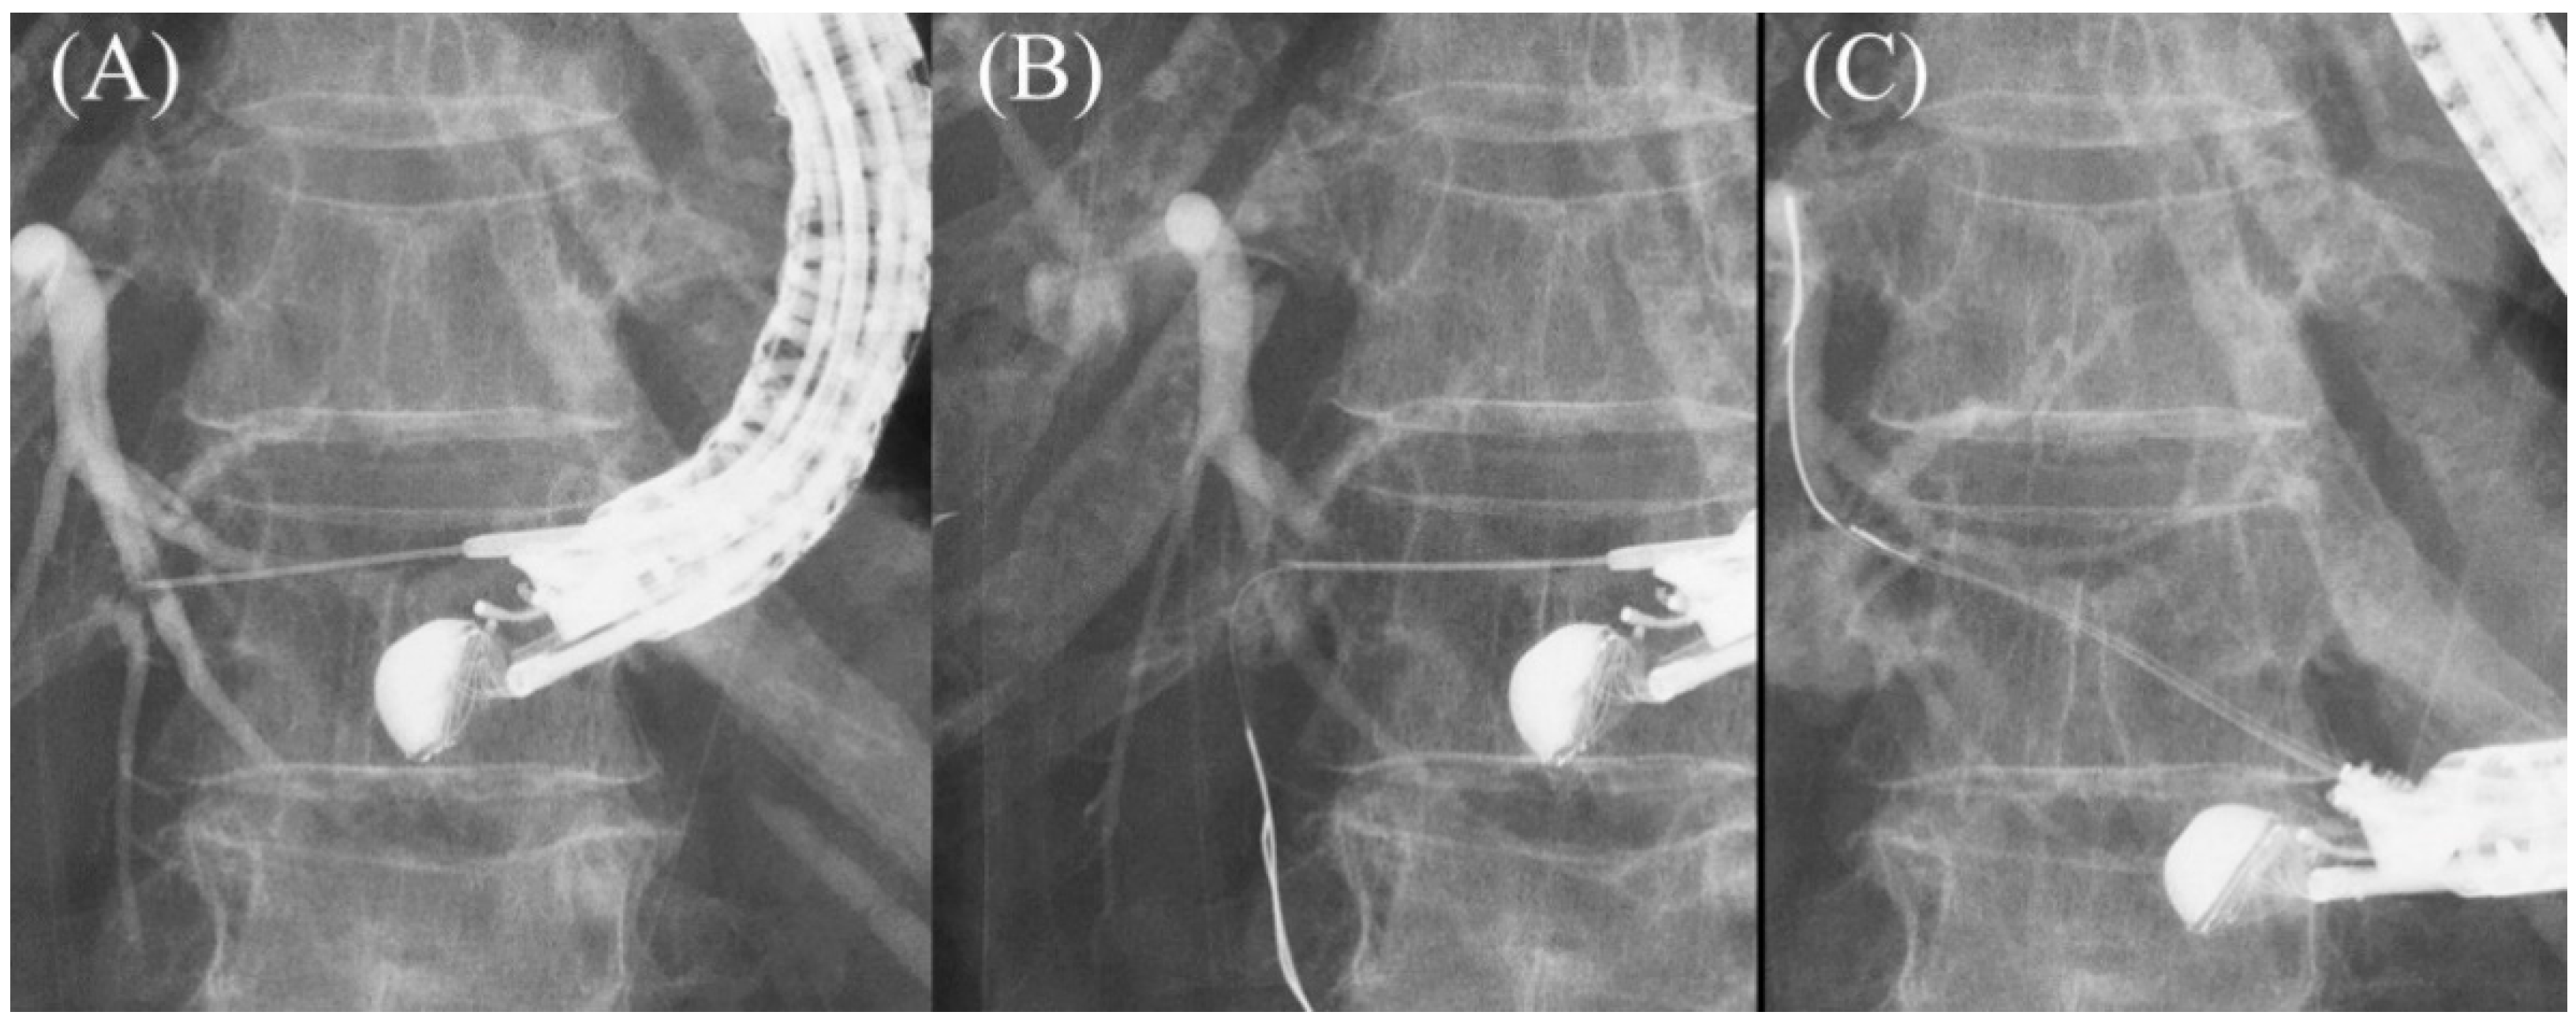

The guidewire is advanced through the needle, and once it enters the bile duct, it is slowly and carefully advanced with gentle rotation to guide it toward the hilar region. If the guidewire is unintentionally advanced to the peripheral side, the “Loop technique” should be attempted first. Push the guidewire with rotation, and when the tip of the guidewire is caught on a lateral branch (Figure 10A), push the guidewire further. Since the tip of the guidewire is fixed, the body of the guidewire will bend with the pushing force and form a loop (Figure 10B). If the loop is facing the hilar region, the guidewire can be advanced to the hilum by pushing further (Figure 10C,D). If the “Loop technique” fails, the “Moving scope technique” is an alternative to change the direction of the guidewire, where pushing the scope while turning the large wheel upward may change the direction of the needle to the cranial side, allowing the guidewire to proceed toward the hilum [39] (Figure 11A–C).

Figure 11.

Moving scope technique for redirection of a guidewire. If a guidewire is unintentionally advanced to the peripheral side (A,B), push the scope while turning the large wheel upward to change the needle direction to the cranial side, allowing the guidewire to proceed toward the hilum (C).